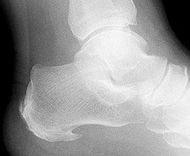

Fasciite plantaire - Épine de Lenoir

Pour venir à bout d’une épine de Lenoir (épine calcanéenne) il faut procéder en plusieurs étapes :

• Eventuelle tension ligamentaire médian du genou coté lésion, gonflement du poplité oui ou non coté lésion, une hypertonie du tendon d’Achille, une rigidité articulaire au niveau Tallus et naviculaire.

1. Vérification articulaire: naviculaire, Tallus, Calcanéum, cuboide.